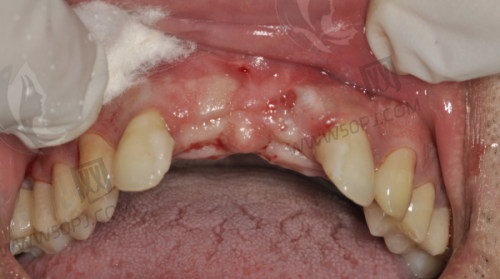

强项:高难度种植、全口修复、吸附性义齿

鼎植口腔在本地做种植牙的人中几乎是“必打卡单位”,医生高振华和黎强在种植牙领域经验颇为丰富,擅长全口吸附性义齿、即刻种植等复杂病例处理。此外,术前会有CBCT影像分析和3D导板定位,精细度特别高。价格一般,活动期间国产种植体可低至2980元/颗。